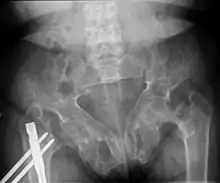

Brown tumors in the pelvis and a hip fracture.[13]

Renal osteodystrophy is usually diagnosed after treatment for end-stage kidney disease begins; however the CKD-MBD starts early in the course of CKD.[1][6] In advanced stages, blood tests will indicate decreased calcium and calcitriol (vitamin D) and increased phosphate, and parathyroid hormone levels. In earlier stages, serum calcium, phosphate levels are normal at the expense of high parathyroid hormone and fibroblast growth factor-23 levels. X-rays will also show bone features of renal osteodystrophy (subperiostic bone resorption, chondrocalcinosis at the knees and pubic symphysis, osteopenia and bone fractures) but may be difficult to differentiate from other conditions. Since the diagnosis of these bone abnormalities cannot be obtained correctly by current clinical, biochemical, and imaging methods (including measurement of bone-mineral density), bone biopsy has been, and still remains, the gold standard analysis for assessing the exact type of renal osteodystrophy.[6][11]